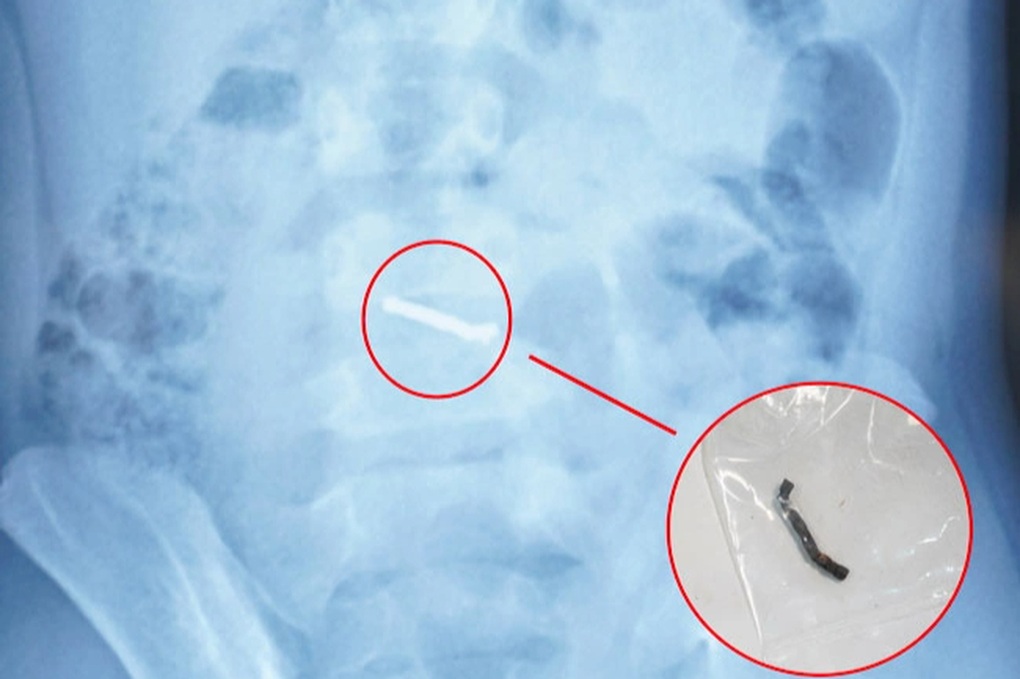

Kết quả tái khám và chụp X-quang phát hiện dị vật “xếp hàng dài” trong ổ bụng trẻ nên được chuyển đến Bệnh viện Nhi Trung ương điều trị.

Hình ảnh dị vật qua chụp X-quang và viên nam châm sau khi được các bác sĩ phẫu thuật lấy ra (Ảnh: Bệnh viện cung cấp).

Trong quá trình phẫu thuật, các bác sĩ phát hiện nhiều viên nam châm nhỏ dính vào nhau thành một chuỗi, gây thủng ruột.

Sau khi xác định dị vật có từ tính và không thể tự đào thải ra ngoài, các bác sĩ đã tiến hành phẫu thuật cho trẻ.